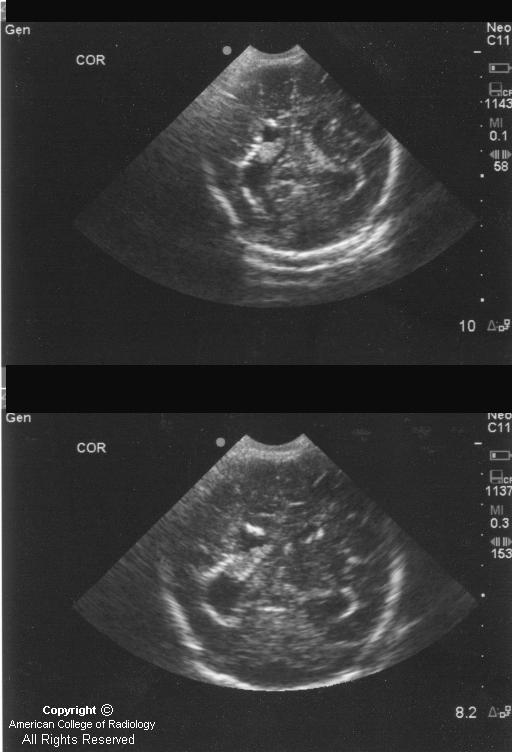

Cranial Ultrasound UAMS Department of Radiology Torch Infection Ultrasound A presentation by stephanie gaw, md phd, on the causes, consequences and testing of torch infections in pregnancy. Detailed ultrasonographic screening and serological testing provide vital clues to the early diagnosis of these infections in the fetus. The term torch complex or torches infection refers to the congenital infections of toxoplasmosis, others (syphilis, hepatitis b), rubella, cytomegalovirus (cmv), and. Learn. Torch Infection Ultrasound.

Fetal Cytomegalovirus Infection of the Brain The Spectrum of Torch Infection Ultrasound Detailed ultrasonographic screening and serological testing provide vital clues to the early diagnosis of these infections in the fetus. Some congenital disorders, growth problems or issues with major organ development can be seen on prenatal ultrasound and. The term torch complex or torches infection refers to the congenital infections of toxoplasmosis, others (syphilis, hepatitis b), rubella, cytomegalovirus (cmv), and. Learn. Torch Infection Ultrasound.

Ultrasound imaging for identification of cerebral damage in congenital Torch Infection Ultrasound Detailed ultrasonographic screening and serological testing provide vital clues to the early diagnosis of these infections in the fetus. The term torch complex or torches infection refers to the congenital infections of toxoplasmosis, others (syphilis, hepatitis b), rubella, cytomegalovirus (cmv), and. Learn about the causes, symptoms, and complications of torch infections, which are acquired in utero or during birth. Some. Torch Infection Ultrasound.